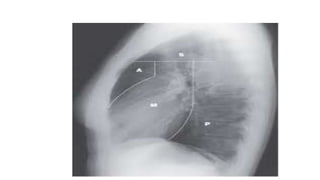

A normal chest x-ray shows the lungs, heart, bones, and soft tissues appearing healthy and unobstructed. The document discusses the different views used in chest x-rays, including PA, AP, lateral, and lateral decubitus views. It also covers topics like depth of inspiration, rotation exposure, the lobes of the lungs, identifying the heart, and how to read a normal chest x-ray.